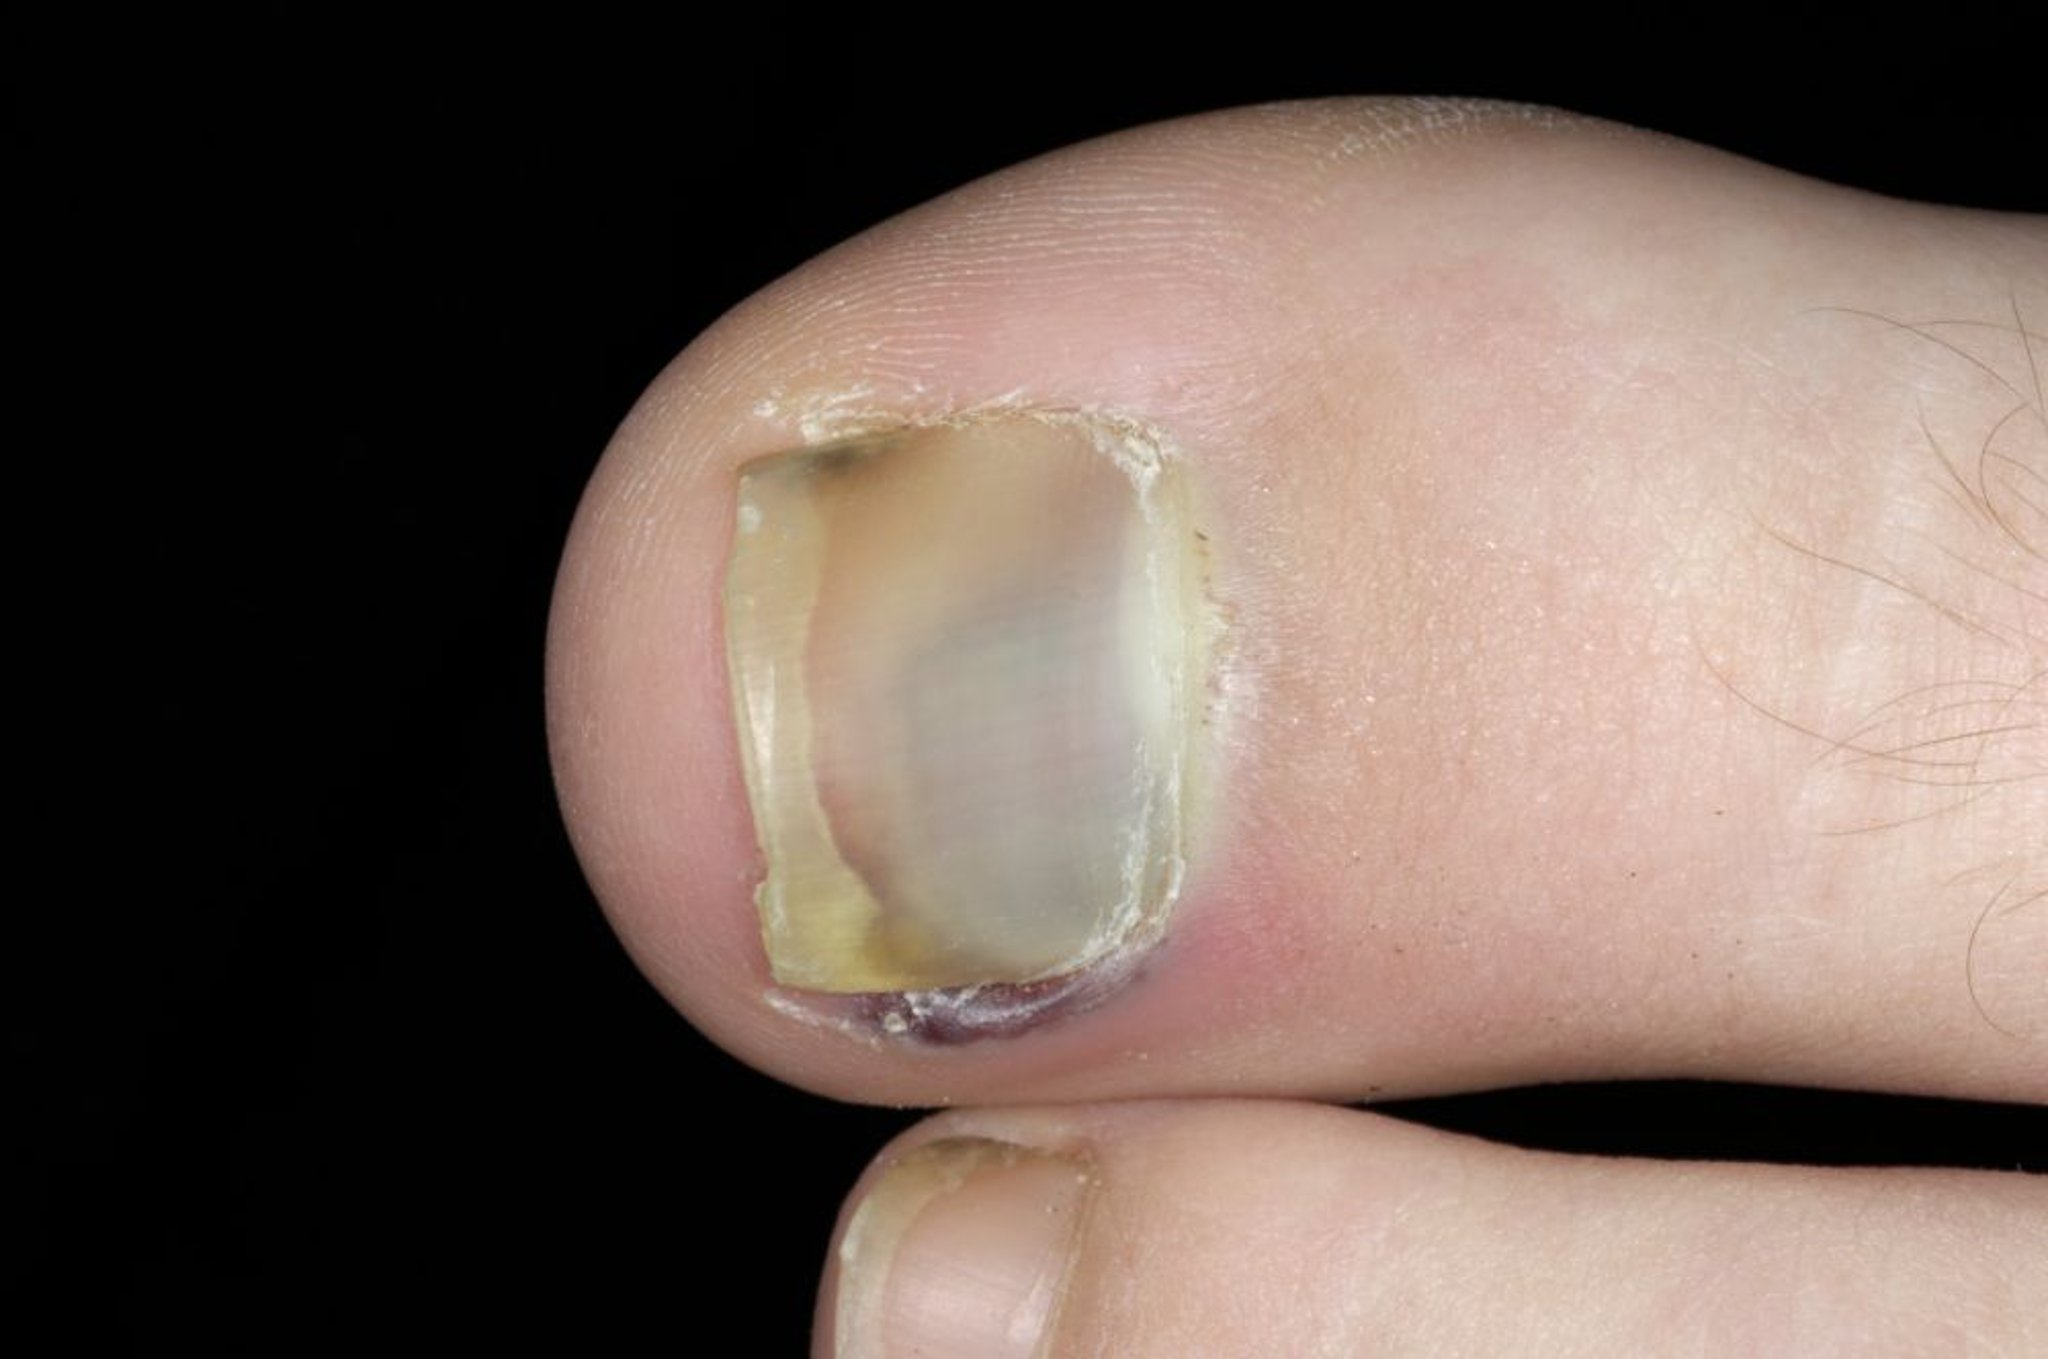

爪下血腫(足趾の爪)

この写真には,母趾の爪の下で生じた出血が写っている。